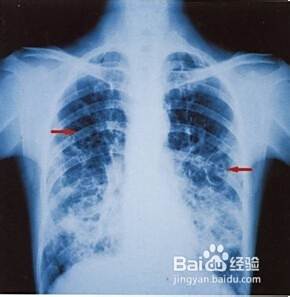

五:狼疮肺。